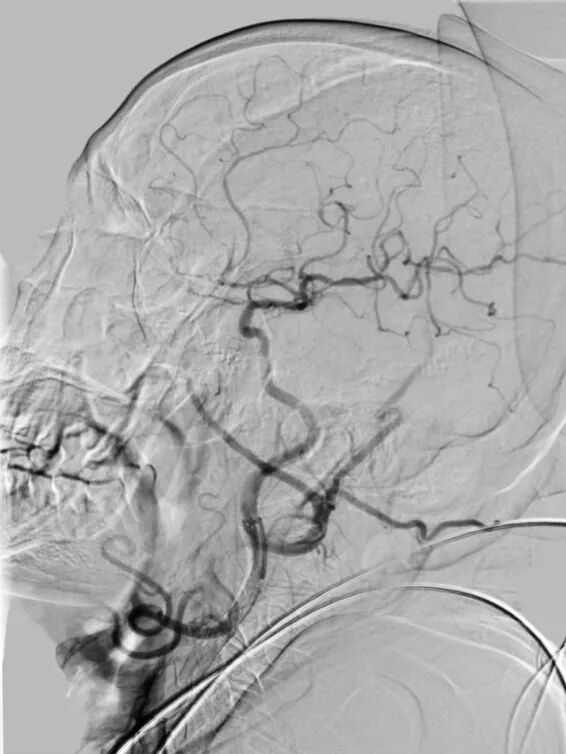

沿保护伞导丝送入4.0mm×30mm球囊,充盈球囊导引导管的球囊阻断血流,于狭窄段定位后命名压扩张球囊,泄球囊时在球囊导引导管的体外端予以负压回抽血液,取出一2mm血栓。经Fluxcap®球囊导引导管输送7.0-10.0mm×40mm自膨支架(Protégé RX)至狭窄段确认位置后释放。应用125cm多功能导管回收保护伞,多功能导管体外端予以负压回抽血液,保护伞内有血栓。

造影可见残余狭窄10%左右,颅内各分支血管通畅。

术后即刻CT:未见明显异常。术后患者症状逐渐好转,出院时NIHSS评分:1分(面瘫1分);继续抗血小板聚集及他汀类药物治疗。